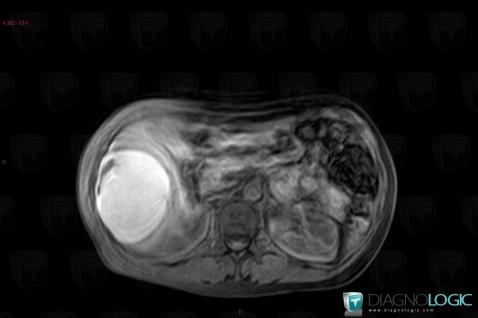

Kyste biliaire, Foie, IRM

Voici les informations spécifiques à l'image clé ci dessus:

- Diagnostic Kyste biliaire, Localisation(s) Foie, comportant les gammes Lésion hépatique en hypersignal T2, Lésion hépatique kystique